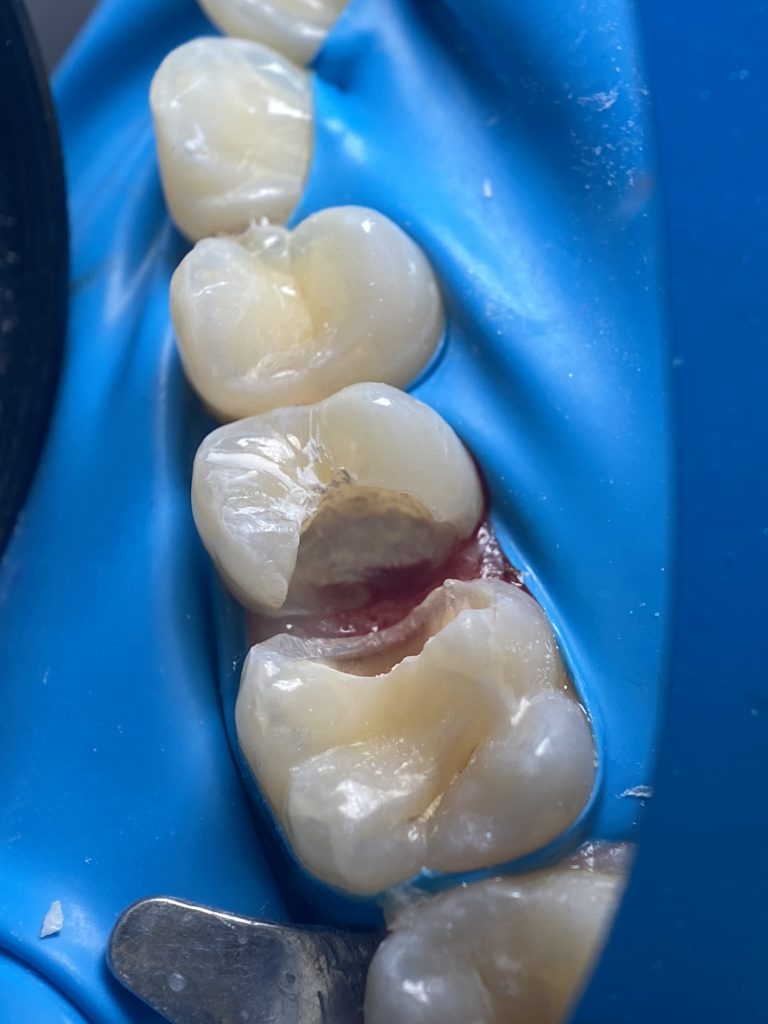

-Coronal pulp removal

-Bleeding control